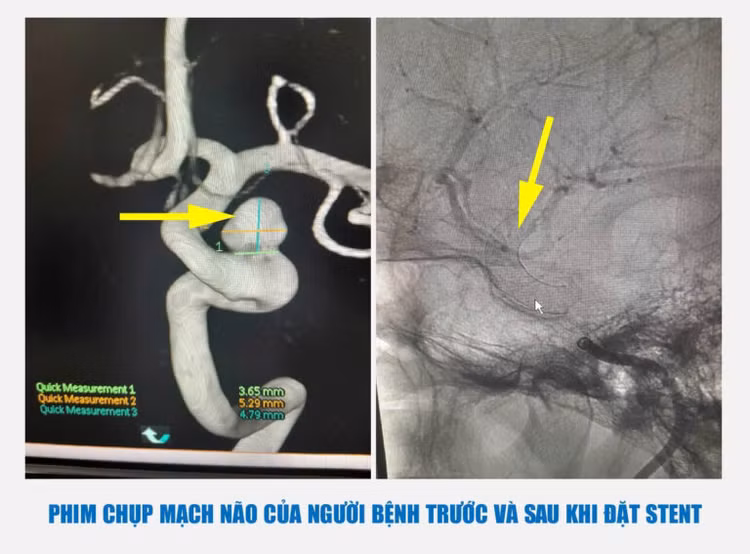

Trường hợp người bệnh T.N.G, 67 tuổi ở (Việt Trì, Phú Thọ) thường xuyên bị đau đầu âm ỉ kéo dài. Người bệnh được khám tại Bệnh viện Đa khoa tỉnh Phú Thọ, kết quả chụp cộng hưởng từ 3.0 phát hiện có túi

Xác định đây là trường hợp phình mạch khó, phức tạp do kích thước túi phình lớn, cổ rộng, không thể can thiệp bằng nút coil thông thường. Các chuyên gia Trung tâm đột quỵ đã hội chẩn đưa ra giải pháp đặt stent chuyển dòng để điều trị cho người bệnh. Kết quả sau can thiệp cắt được dòng máu đi vào trong túi phình và chuyển hướng dòng máu lưu thông tốt qua stent, chỉ 3 ngày sau đó người bệnh được ra viện.